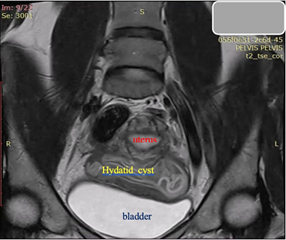

A 23-year-old asymptomatic female patient. During a routine gynecological examination, pelvic ultrasound identified a nonspecific tumor-like mass of solid consistency (Figures 1-3). The patient is sexually active and nulliparous. She has no history of abnormal menstrual bleeding or pelvic pain. Pelvic ultrasonography demonstrated a nonspecific tumor-like mass. The lesion was located in the vesicouterine space, anterior to the uterus (which was in anteversion and anteflexion with length 6.5 cm.) and posterior to the urinary bladder. The mass measured approximately 10 cm and had a predominantly solid component, with multilaminar hypoechoic bands within its capsule (Figures 1 and 4). Both ovaries were visualized and appeared normal on transvaginal ultrasonography (Figures 2 and 3). The pouch of Douglas is free of fluid.

Figure 5. Coronal T2-weighted MRI: The massive cystic formation displaces the bladder ventrally and alters the normal position of the uterus